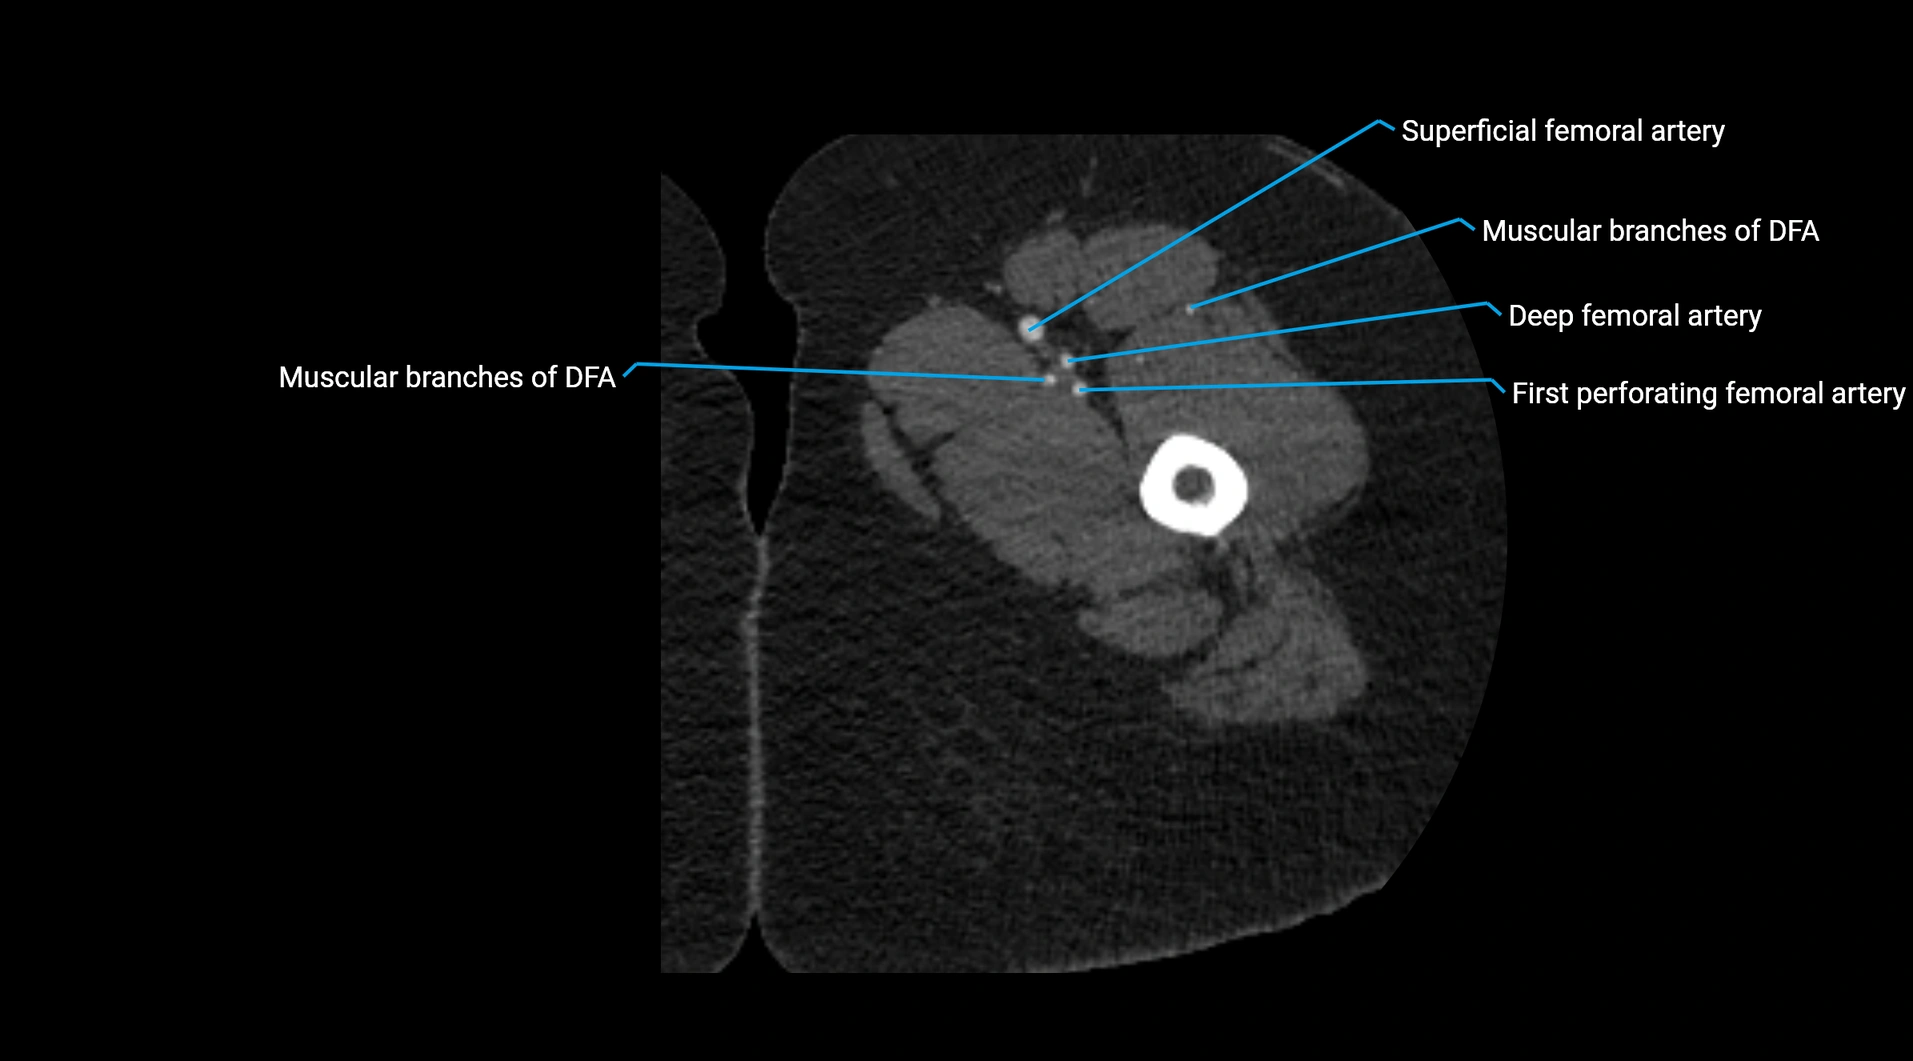

CT images

image